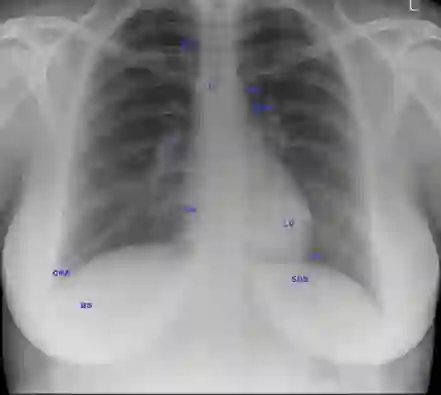

Artificial intelligence in healthcare requires models that are accurate and interpretable. We advance mechanistic interpretability in medical vision by applying Medical Sparse Autoencoders (MedSAEs) to the latent space of MedCLIP, a vision-language model trained on chest radiographs and reports. To quantify interpretability, we propose an evaluation framework that combines correlation metrics, entropy analyzes, and automated neuron naming via the MedGEMMA foundation model. Experiments on the CheXpert dataset show that MedSAE neurons achieve higher monosemanticity and interpretability than raw MedCLIP features. Our findings bridge high-performing medical AI and transparency, offering a scalable step toward clinically reliable representations.